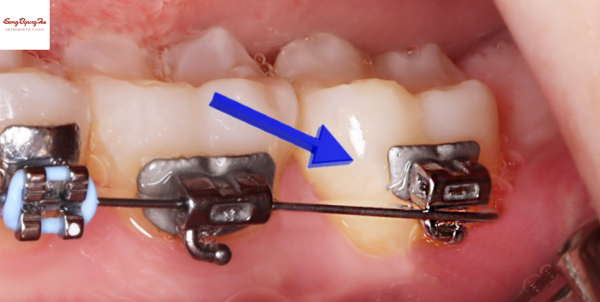

철사 '끝'이 찔리는 경우 외에도

아래 사진과 같이

브라켓이 떨어져서 움직이는 경우가 있습니다.

마찬가지로 이런 경우에도 왁스를 붙여서 당장의 불편함은 해결 가능합니다.